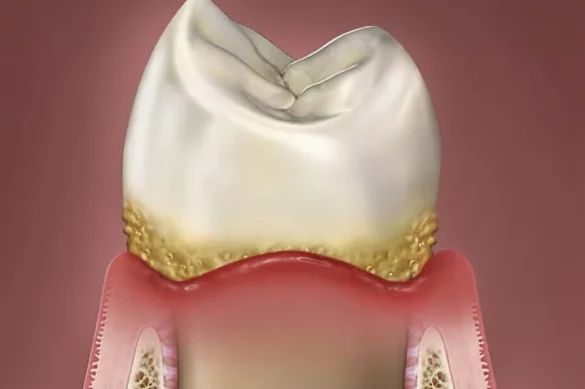

Periodontal disease is an infection of the gums and surrounding tissues that support the teeth. It typically starts with gingivitis, the mildest form, which causes redness, swelling, and bleeding gums. If left untreated, it can progress to periodontitis, which destroys the bone and connective tissue holding your teeth in place. Advanced stages can result in loose or lost teeth and chronic pain.

The main cause of periodontal disease is poor oral hygiene. When plaque—a sticky film of bacteria—builds up on teeth, it leads to inflammation and infection in the gums. Other risk factors include:

To manage periodontal disease effectively, you need to recognize its early warning signs:

- Bleeding gums when brushing or flossing

- Persistent bad breath

- Swollen or red gums

- Receding gums (teeth looking longer)

- Loose teeth

- Pain while chewing

- Deep pockets forming between gums and teeth